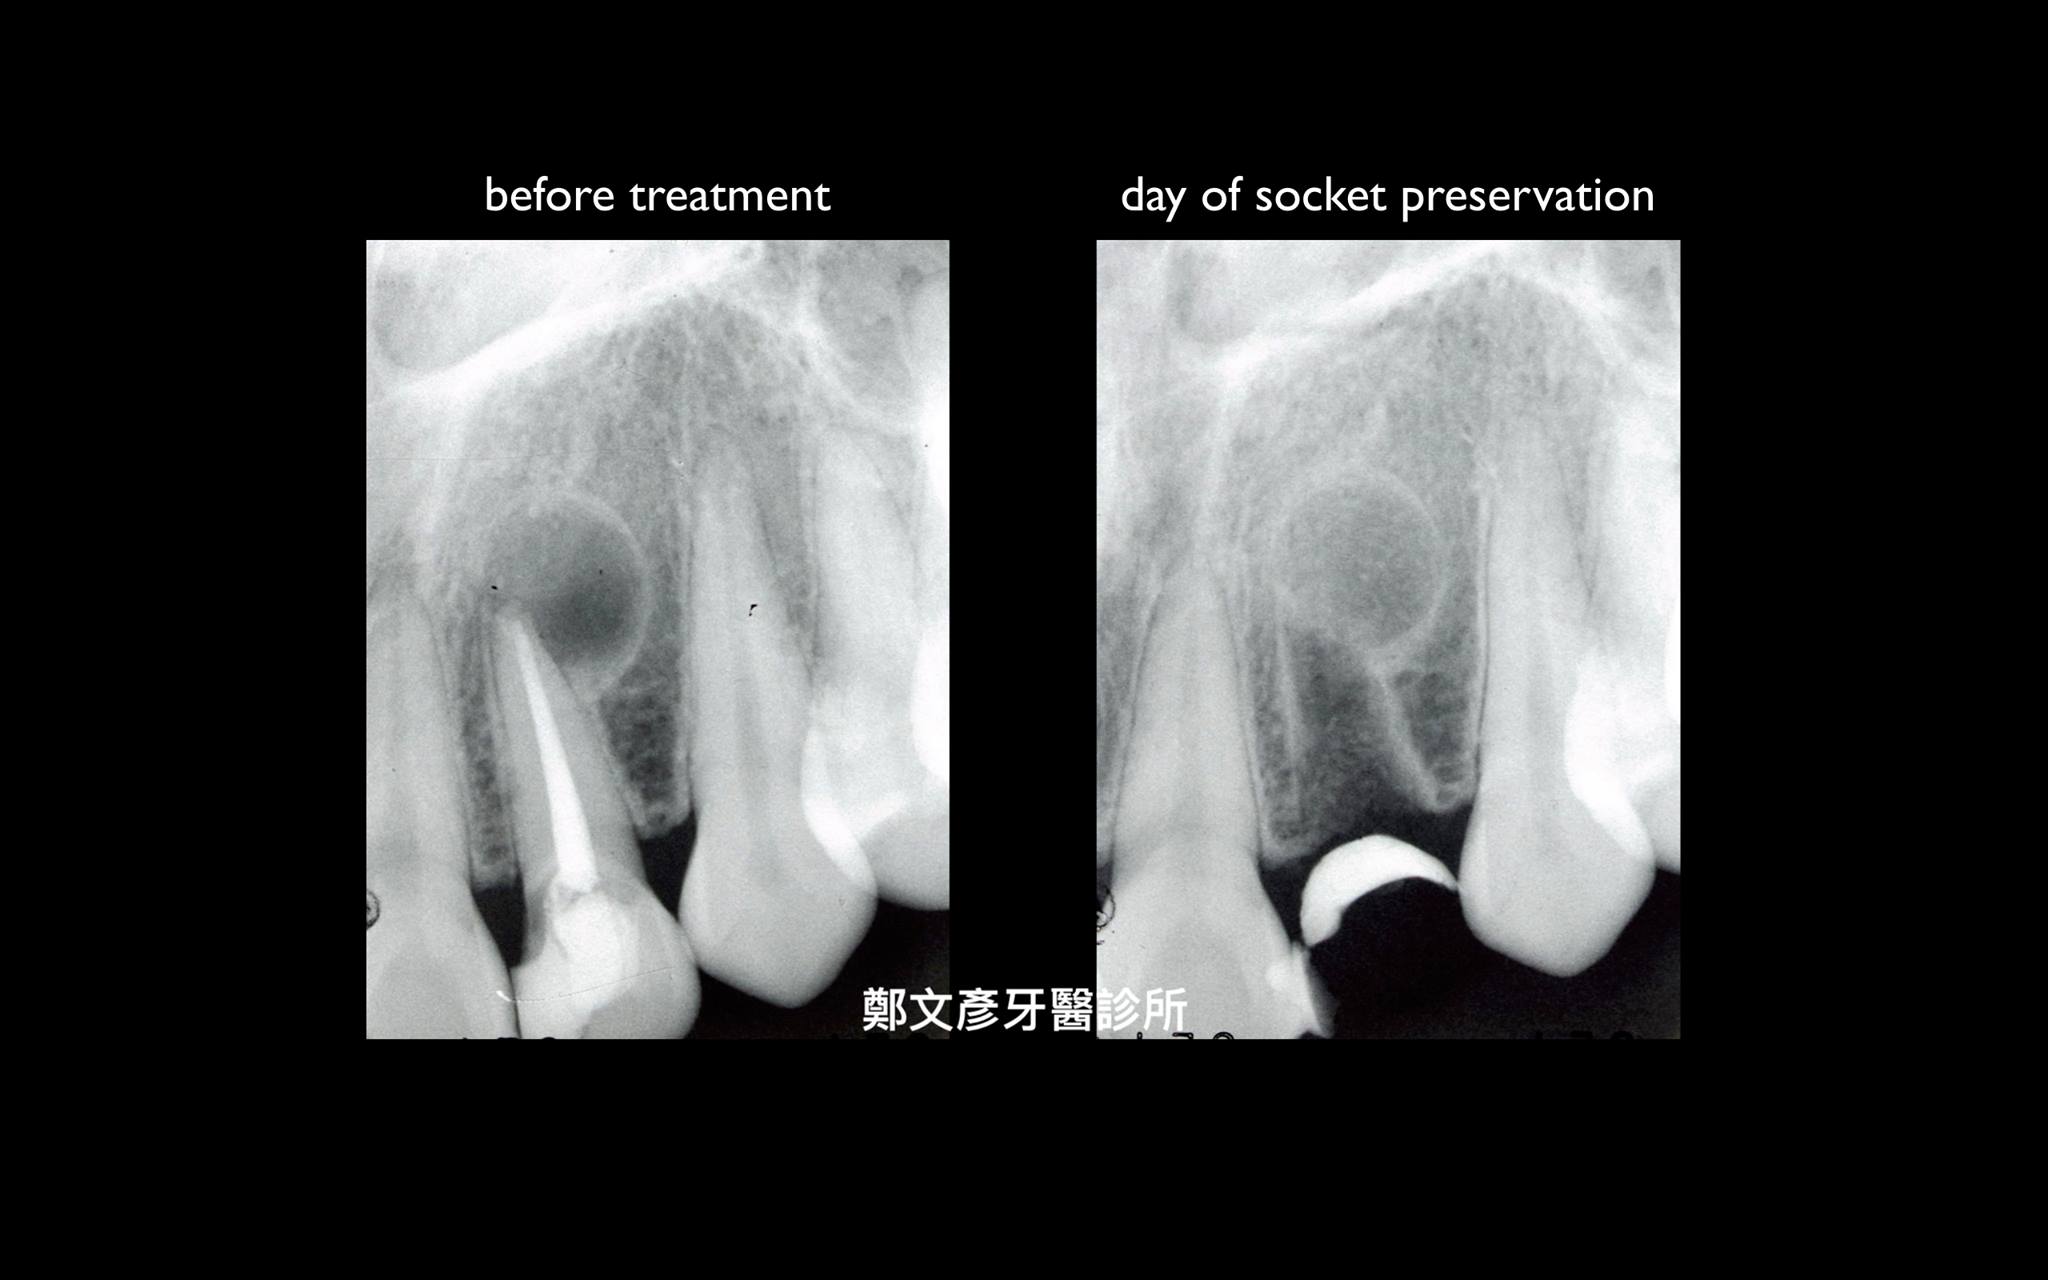

前牙植牙美學及軟組織轉移

植牙美學